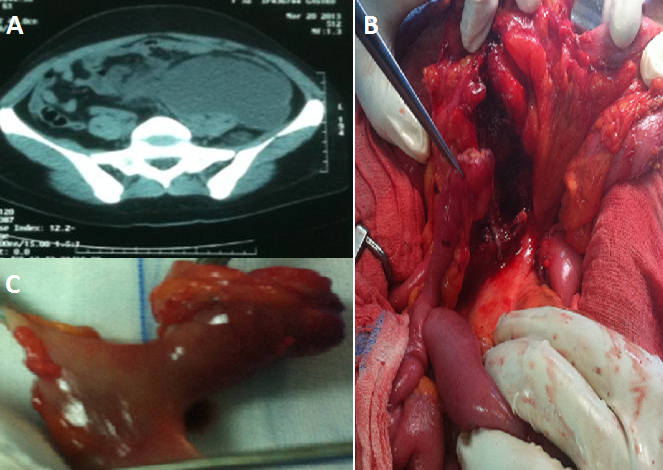

Le diverticule de Meckel est une anomalie congénitale résultant d'une résorption incomplète du canal omphalo-mésentérique, pouvant se compliquer dans 4% des cas. Il s'agit d'une patiente âgée de 48 ans, sans antécédent pathologique, admise aux urgences pour des douleurs abdominales généralisées à point de départ hypogastrique. L'examen clinique trouvait une sensibilité abdominale généralisée chez une patiente fébrile à 38,7 c. Le bilan biologique avait montré une hyperleucocytose à 18000/mm3, avec une CRP à 130 mg/l. L'échographie avait objectivé un épanchement intra péritonéal de moyenne abondance. Un complément scannographique avait mis en évidence une énorme collection rétro péritonéale refoulant le colon gauche et l'intestin grêle, avec une distension grêlique (A). La patiente a été opérée par laparotomie médiane, avec découverte d'un volumineux abcès rétro péritonéal en rapport avec un diverticule de Meckel situé à 90 cm de la valvule iléo caecal, et perforé au niveau de sa pointe dans le rétro péritoine (B). On a réalisé une résection grêlique emportant le diverticule avec double stomie grêlo- grêlique à la Bouilly-Walkman associée à une aspiration de l'abcès puis lavage et drainage péritonéal large (C). Les suites post opératoires ont été simples, avec rétablissement de la continuité digestive après deux mois. L'étude anatomo pathologique de la pièce de résection est revenue en faveur d'une diverticulite Chronique sans signe de malignité.